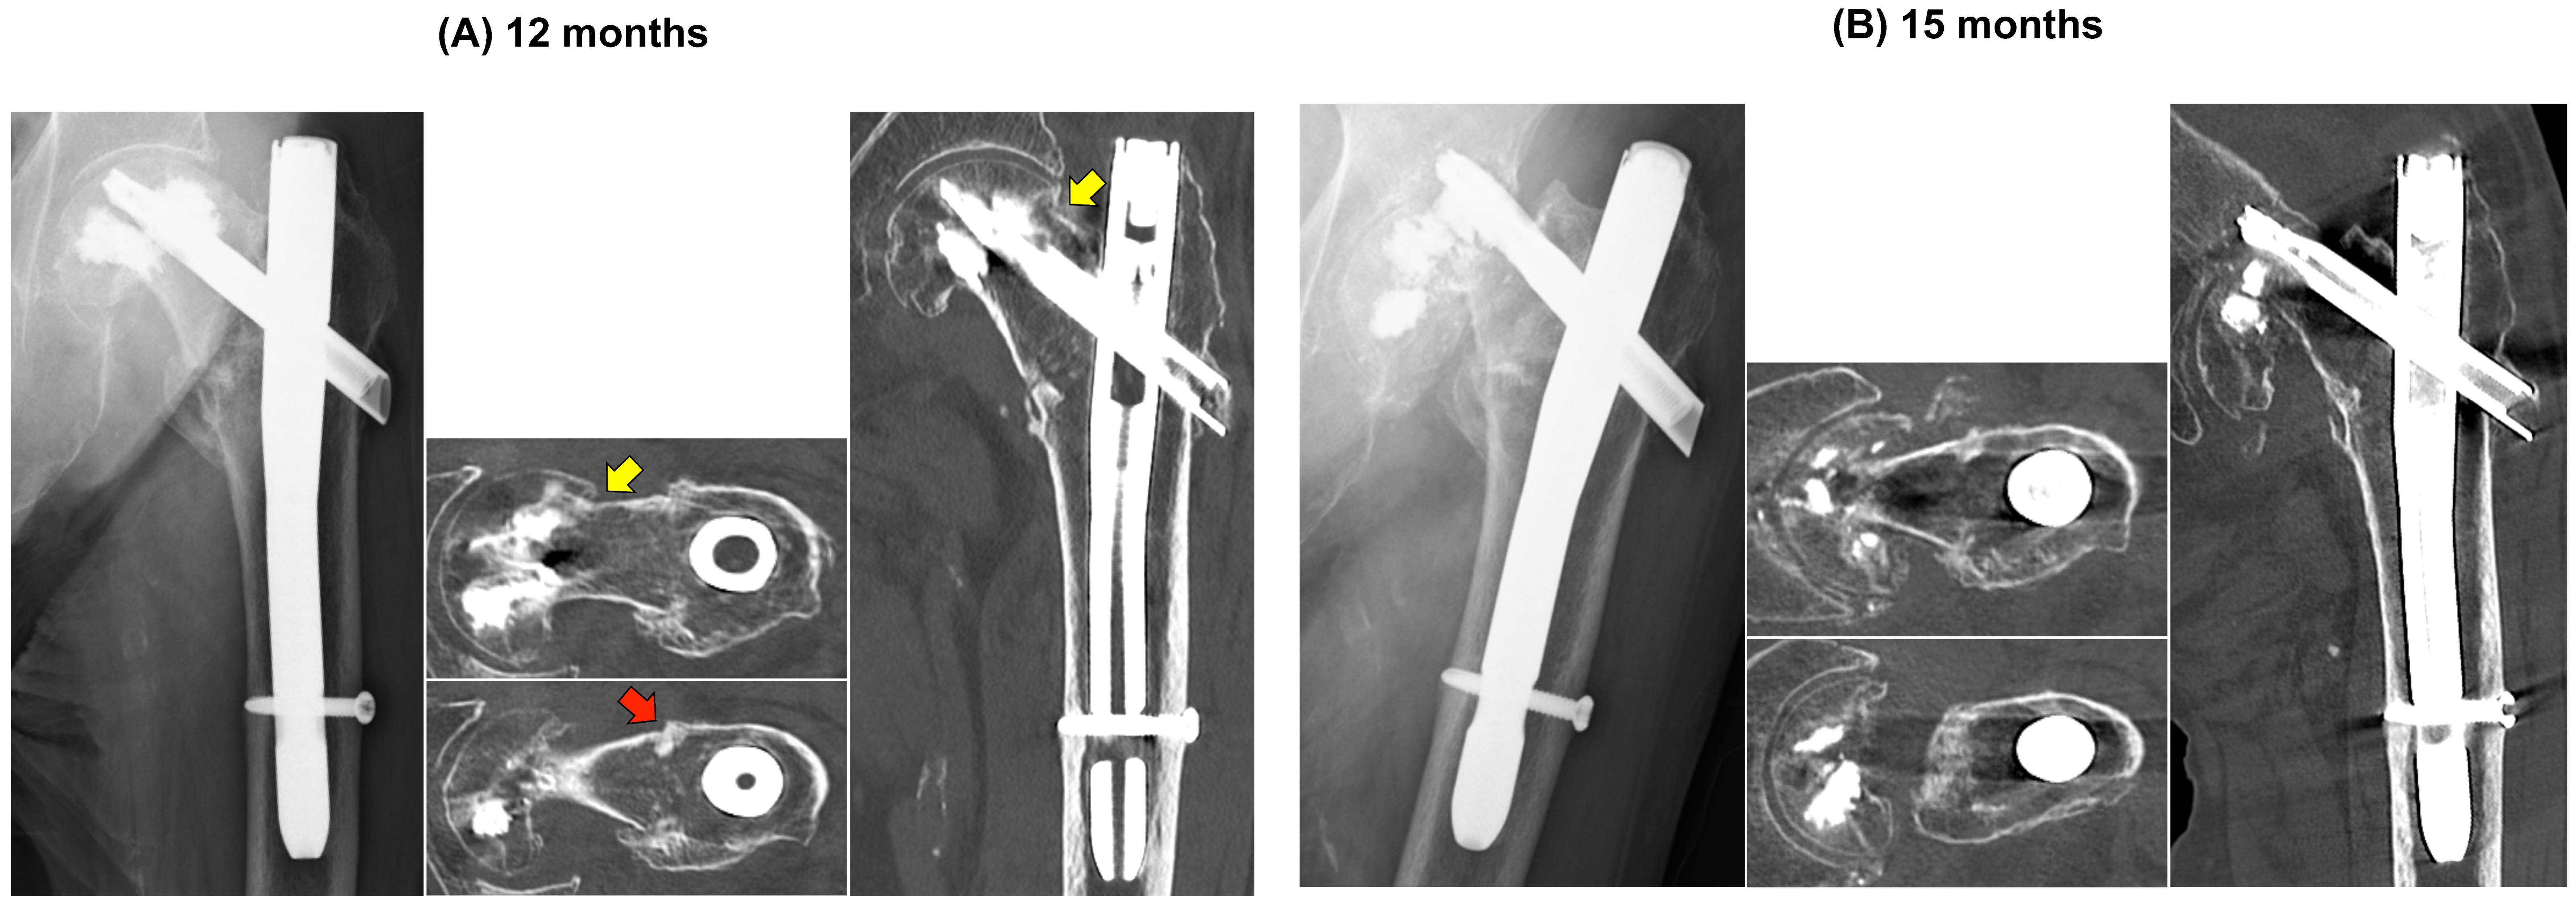

At 12 months, radiographs demonstrated a pronounced head–neck varus tilt relative to the shaft, with en bloc cephalad migration of the blade and superior cement mantle and no interval barrel-based telescoping, consistent with evolving subcapital failure rather than intertrochanteric collapse (Figure 4A). Given the modest activity-related discomfort and the patient’s preference to avoid further surgery, we adopted close clinical and radiographic surveillance with WBAT. At 15 months, the patient’s groin pain had acutely worsened without new trauma, and imaging confirmed an ipsilateral subcapital femoral neck fracture with marked fragmentation adjacent to the cement-augmented head (Figure 4B). Representative axial and coronal CT reconstructions at failure delineated the fracture geometry and spatial relationships between the residual head fragments, cement mantle, and implants. Because of extensive fragmentation and metal–cement artifacts, formal NSA/TAD measurements at the time of failure were not feasible.

Figure 4. 12- and 15-month imaging: progression to a subcapital femoral neck fracture. (A) 12 months: AP radiograph shows pronounced head–neck varus with en bloc blade–superior cement mantle migration and no interval barrel-based telescoping. Axial CT at 12 months demonstrates a linear superior subcapital sclerotic band (yellow arrow) and shows union across the intertrochanteric region (red arrow). (B) 15 months: AP radiograph and CT reconstructions—axial and coronal, bone window—confirm an ipsilateral subcapital femoral neck fracture with fragmentation; the intertrochanteric region remains united.